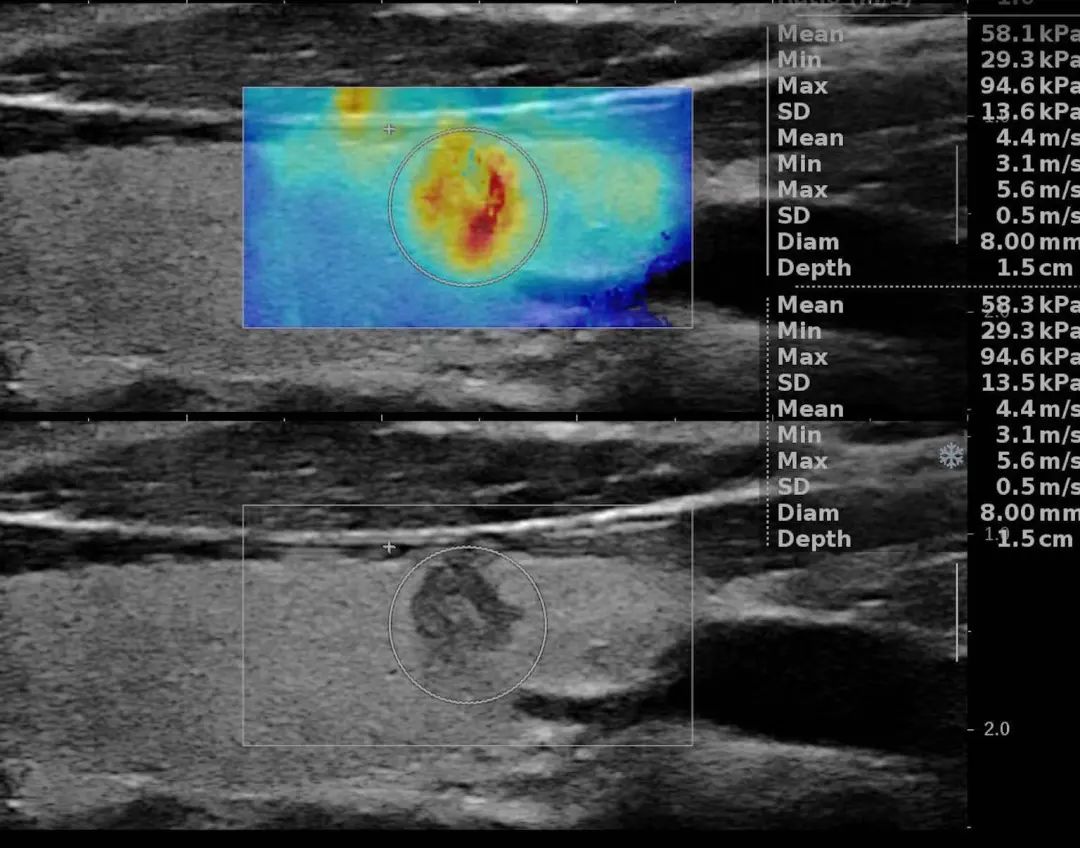

C- TIRADS(中国甲状腺结节分级指南)精读及效能对比(图1)C- TIRADS(中国甲状腺结节分级指南)精读及效能对比(图2)C- TIRADS(中国甲状腺结节分级指南)精读及效能对比(图3)C- TIRADS(中国甲状腺结节分级指南)精读及效能对比(图4)C- TIRADS(中国甲状腺结节分级指南)精读及效能对比(图5)C- TIRADS(中国甲状腺结节分级指南)精读及效能对比(图6)C- TIRADS(中国甲状腺结节分级指南)精读及效能对比(图7)C- TIRADS(中国甲状腺结节分级指南)精读及效能对比(图8)甲状腺乳头状微小癌剪切波和二维图像对比